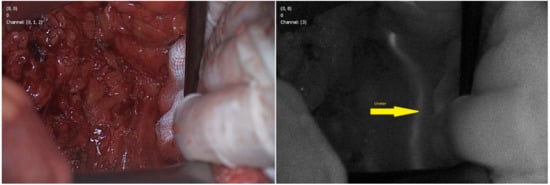

- Barnes, T.G.; Hompes, R.; Birks, J.; Mortensen, N.J.; Jones, O.; Lindsey, I.; Guy, R.; George, B.; Cunningham, C.; Yeung, T.M. Methylene blue fluorescence of the ureter during colorectal surgery. Surg. Endosc. 2018. [Google Scholar] [CrossRef] [PubMed]

- Verbeek, F.P.R.; Van der Vorst, J.R.; Schaafsma, B.E.; Swijnenburg, R.J.; Gaarenstroom, K.N.; Elzevier, H.W.; van de Velde, C.J.; Frangioni, J.V.; Vahrmeijer, A.L. Intraoperative near infrared fluorescence guided identification of the ureters using low dose methylene blue: A first in human experience. J. Urol. 2013. [Google Scholar] [CrossRef]

- Al-Taher, M.; van den Bos, J.; Schols, R.M.; Bouvy, N.D.; Stassen, L.P.S. Fluorescence Ureteral Visualization in Human Laparoscopic Colorectal Surgery Using Methylene Blue. J. Laparoendosc. Adv. Surg. Tech. 2016. [Google Scholar] [CrossRef] [PubMed]

- Yeung, T.M.; Volpi, D.; Tullis, I.D.C.; Nicholson, G.A.; Buchs, N.; Cunningham, C.; Guy, R.; Lindsey, I.; George, B.; Jones, O.; et al. Identifying ureters in situ under fluorescence during laparoscopic and open colorectal surgery. Ann. Surg. 2016. [Google Scholar] [CrossRef] [PubMed]

- Matsui, A.; Tanaka, E.; Choi, H.S.; Kianzad, V.; Gioux, S.; Lomnes, S.J.; Frangioni, J.V. Real-time, near-infrared, fluorescence-guided identification of the ureters using methylene blue. Surgery 2010. [Google Scholar] [CrossRef]